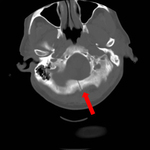

Axial CT scan showing nondepressed linear skull fracture (arrow) of the skull base involving the foramen magnum. This injury pattern is concerning for associated spinal fracture, cord injury, and blunt cerebrovascular injury